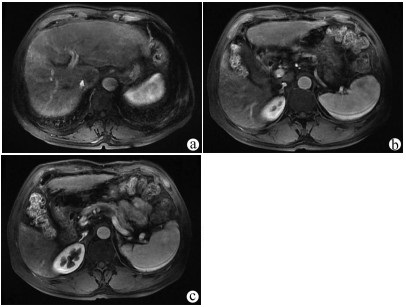

Guideline for ultrasonic diagnosis of liver diseases

Chinese Society of Ultrasound in Medicine, Oncology Intervention Committee of Chinese Research Hospital Society, National Health Commission Capacity Building and Continuing Education Expert Committee on Ultrasonic Diagnosis

2021, 37(8): 1770-1785. DOI: 10.3969/j.issn.1001-5256.2021.08.007

Abstract(3025) HTML (6526) PDF (9311KB)(794)

Abstract:

Ultrasound is a non-invasive, real-time, inexpensive, radiation-free and easily repeatable method, usually used for liver imaging. In recent years, new ultrasound examination techniques for liver diseases such as contrast-enhanced ultrasound and elastography have been rapidly developed, which can effectively identify intrahepatic space-occupying lesions, assess the degree of liver fibrosis and portal hypertension, and monitor the effects of treatment. Therefore, these technologies play an important diagnostic role in clinical liver diseases and have therapeutic interventional value. This guideline classifies the instrument set-up, patient preparation, and physician examination methods through multimodal ultrasound examinations (gray-scale ultrasound, color Doppler ultrasound, contrast-enhanced ultrasound, elastic ultrasound) for liver diseases. In addition, liver diseases multimodal ultrasound technology diagnostic criteria for diffuse hepatic lesions (inflammatory lesions, fibrosis, and sclerosis), multiple space-occupying lesions, and interventional procedures have been defined and standardized. Concurrently, we also recommend the ultrasound monitoring time interval and diagnostic report writing standard for liver diseases.